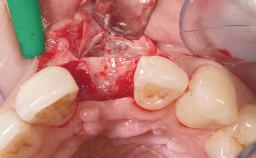

Immediate Placement of an Implant in a Maxillary Right Central Incisor Site

A 30-year-old female patient was referred to the office for the treatment of tooth 11. Her chief concern at the initial visit was to inquire, “Why is my tooth pink?” Upon clinical examination, it was determined that tooth 11 had a previous history of trauma and that the clinical crown had become noticeably pink in color as a result of internal resorption. This diagnosis was confirmed radiographically, indicating a large radiolucency involving the central and distal portions of the clinical crown. It was determined that restoration of this tooth was not possible, and that extraction was indicated. The presence of a mid-line diastema, which the patient wanted to reproduce, directed the treatment plan for tooth replacement utilizing a dental implant.

Bone Augmentation Horizontal|Simultaneous

Augmentation Materials Autogenous chips|Membrane